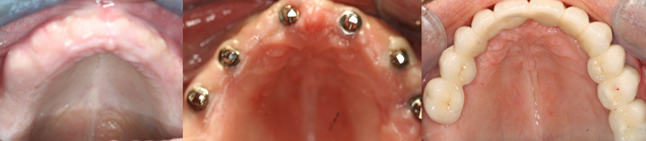

FULL ARCH DENTAL IMPLANT

Extensively damaged or missing teeth can not only impede you from living a fulfilling life but can also affect your health and confidence. But full arch mouth reconstruction solution, using implants can be used to support ill-fitting dentures or restore the entire arch with a bridge to improve appearance and reinstate complete oral functions.

4-6 implants are placed in each jaw an aesthetic, functional bridge is fabricated over the implants. It need not be removed to clean on a daily basis and is probably the closest to natural teeth in function and aesthetics.

2-4 implants are placed in the lower jaw, 4-6 implants in the upper jaw can support a full denture. This procedure is very economical, greatly improves retention, stability and function. All of these stages can be carried out in the single appointment depending on need and condition of the patient.

IMPLANT SUPPORTED DENTURE

Card image Actual Practice Photographs ©Dr.Pavan Bopanna